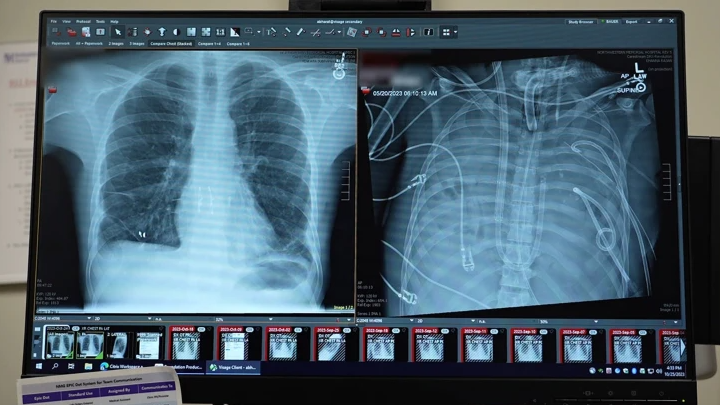

Radiografias mostram os pulmões novos (à esquerda) e os pulmões antigos (à direita) do doente de 33 anos. Crédito: Northwestern Medicine, via Nature